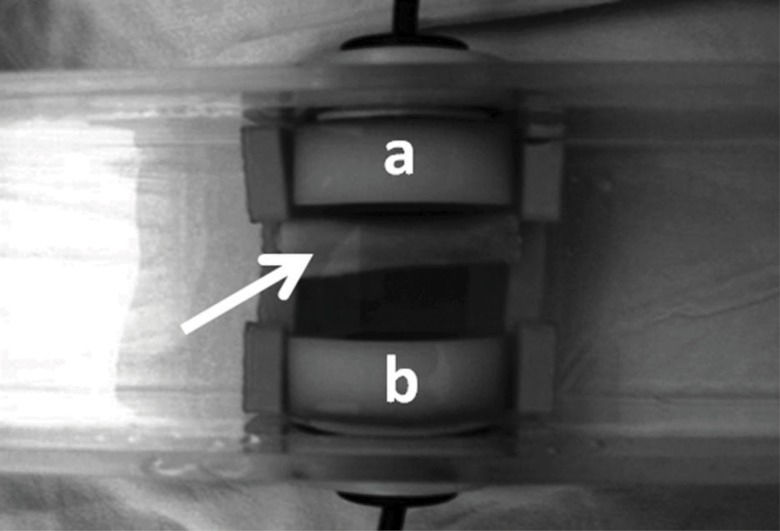

UltrasonometryTransverse underwater UV was measured with the bone segments immersed in an acoustic tank that was adapted with two unfocused ultrasound transducers (2 mm-thick PZT-5 disc, 12 mm in diameter, 1 MHz frequency), one on each of the tank in the geometric center of the walls and separated by a 25 mm distance but precisely aligned with each other along the central longitudinal axis (Figure 3). To record measurements, the two transducers, one for US wave emission and the other for reception, were connected to an ultrasound generator-receiver amplifier source (Biotecnosis do Brasil Ltda., Model US01, Ribeirão Preto, São Paulo, Brazil, www.biotecnosis.com) that could generate high power (up to 300 V) narrow (1 µs) well-defined ultrasonic pulses. The source was linked to a computer loaded with software to automatically calculate the UV based on the time of flight of the first arrived signal (FAS), as observed on a digital storage oscilloscope (Agilent Technologies, Inc., model DSO3062A, Shangai, China), together with the emitted ultrasound signal.

The FAS was defined as the first 5% positive deflection above baseline preceding the signal corresponding to the transmission mean (water) (Figure 4). The equipment was calibrated after every five measurements with a 20-mm-thick Teflon disc (constant 1274 m/s UV, at 35°C, 0.3% variation) to check for regularity and accuracy. The bone segments were positioned lengthwise in the acoustic tank supported by a Teflon stand on each end, transverse to the transducers and with the midpoint of the bone segment precisely aligned with the central axis of both transducers but closer to the emitting transducer than to the receiving transducer. The ultrasound emission frequency was 1 MHz, the pulse duration was ±1 μs, the rise time was ±0.1 ns, and the repetition time was 1 s. UV was calculated according to the formula:

Five consecutive measurements were made at 5-minute intervals, the lowest and highest values were discarded, and the mean of the three remaining values was used for statistical comparisons.

Accordingly, we used the underwater transverse ultrasonometry modality exactly as used in our previous investigations. In this method, both emitting and receiving transducers are focused on the region of interest of the analyzed bone segment and the ultrasonic waves cross the entire bone from side to side, thus providing a more complete evaluation of the entire bone thickness and likely a more accurate measure of the UV. Actually, in the longitudinal modality, the ultrasound waves tend to run superficially, thus only evaluating the subperiosteal layer of the entry cortex depending on the US frequency/wavelength. It is well known that, for a normal (90°) ultrasound incidence, the ultrasound waves travel superficially if the wavelength is smaller than the thickness of the cortex, thus providing no information pertaining to the deep parts of the specimen. A more complete evaluation can be performed when the wavelength is greater than the thickness of the cortex, a situation in which the ultrasound waves travel through the entire cortex thickness 32. The 1 MHz frequency emission used here produced ultrasound waves of 1.5 mm wavelength, which is approximately the thickness of the cortex of the analyzed bones, therefore indicating that the emitted ultrasound waves were capable of travelling through the entire thickness.

However, the cylindrical shape of the bone shaft imposes a ring-fashion pattern to the wave propagation by which the waves running along both the anterior and posterior cortices exit on the opposite side of the emission together with a few waves that manage to pass directly through the bone marrow at a lower UV 33.